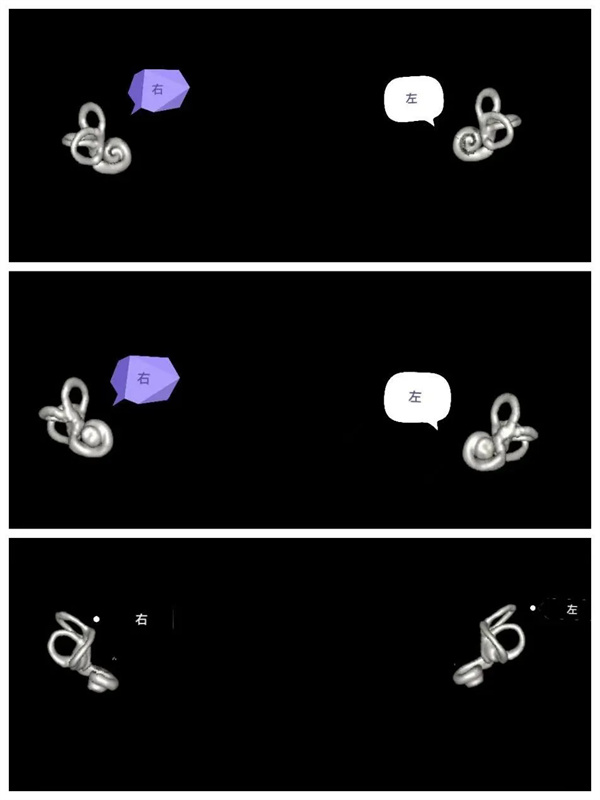

圖6:MIP圖,完美顯示雙側(cè)內(nèi)耳解剖輪廓。

圖7:VR圖,雙側(cè)內(nèi)耳解剖輪廓圖的不同角度顯示圖(后面觀,前面觀,上面觀)。

圖8:VR圖,單側(cè)內(nèi)耳解剖輪廓前面和側(cè)面圖。